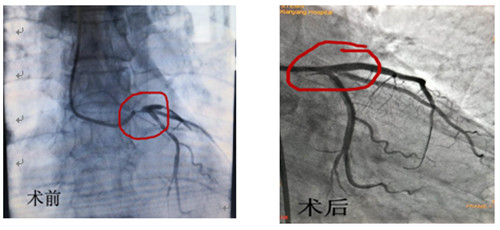

术前术后造影对比

12月16日早上8点30分手术如期进行,术前IVUS评估:左主干自口部至末端弥漫狭窄,最小管腔面积<1mm2,斑块负荷程度>90%,主要为纤维脂质斑块,无明显钙化,回旋支开口尚可,前降支近段主要为纤维脂质斑块,亦无明显钙化。据此,手术方案定为:前降支近段至左主干口部串联植入2枚支架,回旋支近段1枚支架,无需旋磨、切割,支架植入后IVUS评估:支架膨胀、贴壁良好,左主干口部支架梁覆盖完全,手术完美收官。此系心内二病区左梅主任及其团队在导管室配合下完成的我院首例自主IVUS指导下左主干PCI。